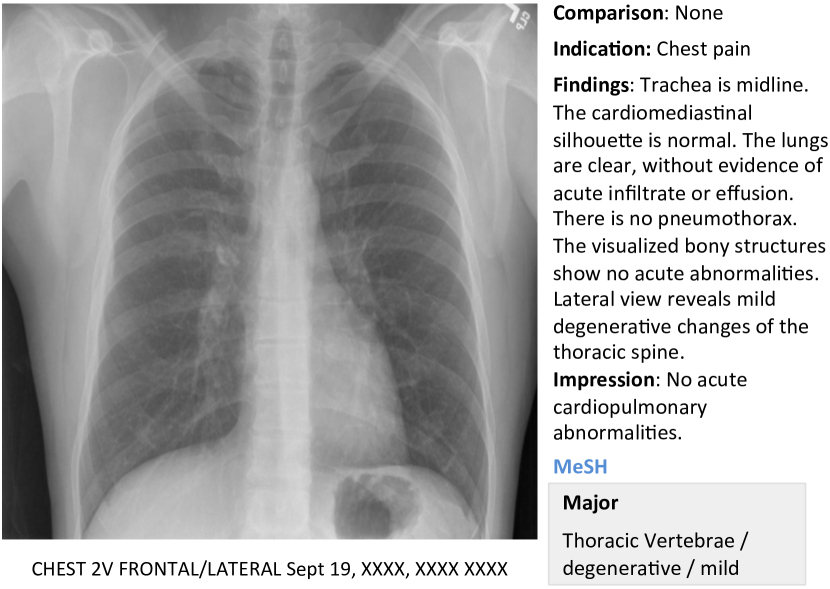

In this work, we demonstrate how to automatically annotate chest x-rays with diseases along with describing the contexts of a disease, e.g., location, severity, and the affected organs. A publicly available radiology dataset is exploited which contains chest x-ray images and reports published on the Web as a part of the OpenI [2] open source literature and biomedical image collections. An example of a chest x-ray image, report, and annotations available on OpenI is shown in Figure 1.

We use a publicly available radiology dataset of chest x-rays and reports that is a subset of the OpenI [2] open source literature and biomedical image collections. It contains 3,955 radiology reports from the Indiana Network for Patient Care, and 7,470 associated chest x-rays from the hospitals’ picture archiving systems. The entire dataset has been fully anonymized via an aggressive anonymization scheme, which achieved 100% precision in de-identification. However, a few findings have been rendered uninterpretable. More details about the dataset and the anonymization procedure can be found in [11], and an example case of the dataset is shown in Figure 1.

Each report is structured as comparison, indication, findings, and impression sections, in line with a common radiology reporting format for diagnostic chest x-rays. In the example shown in Figure 1, we observe an error resulting from the aggressive automated de-identification scheme. A word possibly indicating a disease was falsely detected as a personal information, and was thereby “anonymized” as “XXXX”. While radiology reports contain comprehensive information about the image and the patient, they may also contain information that cannot be inferred from the image content. For instance, in the example shown in Figure 1, it is probably impossible to determine that the image is of a Burmese male.

On the other hand, a manual annotation of MEDLINE ® citations with controlled vocabulary terms (Medical Subject Headings (MeSH®) [1]) is known to significantly improve the quality of the image retrieval results [20, 22, 10]. MeSH terms for each radiology report in OpenI (available for public use) are annotated according to the process described in [12]. We use these to train our model.